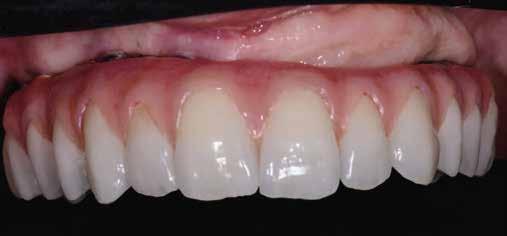

értünk el (19. ábra). Az okkluzális nyílást tefloncsíkkal és kompozittal zártuk (20. ábra). Mindezek után, posztoperatív kontroll röntgenfelvétel készült, amely a pótlás megfelelő illeszkedését mutatta (21. ábra). A hat hónapos utánkövetés során jól megfigyelhető a teltebb lágyszöveti profil és a megtartott kresztális csontszint (22–24. ábra)

„tekercslebeny” (roll flap), szubkresztális implantátumbehelyezés a biológiai szélesség megtartása érdekében és az egyedi ínyformázó. Az alkalmazott implantátumrendszert az egyedülálló osseo-connect felület (OCS) miatt választottuk ki, valamint azért, mert az implantátum nyaka támogatja a lágyszöveti zárást, megelőzve a bakteriális beszivárgást, ami védi az implantátumot. A homokfúvott és maratott felület elősegíti a gyors csontosodást. Az implantátum gyökér formájú (tapered), és dupla önvágó kompressziós menettel rendelkezik, amelyek fontosak a magas primer stabilitás eléréséhez. A copaSKY implantátumrendszer platform switchinget alkalmaz a kresztális csontvesztés minimalizálása érdekében, mivel ez kulcsfontosságú az implantátum hosszú távú sikeréhez és stabilitásához. Az önmetsző kettős menet gyorsabb implantátumbehelyezést biztosít alacsonyabb hőtermelés és csontkondenzáció mellett [7]. A homokfúvott és savmaratott, önmetsző menettel ellátott, cilindrikus és egyben gyökér formájú hibrid kialakítású implantátumok statisztikailag nagyobb behelyezési és eltávolítási nyomatékot mutatnak az esztergált implantátumokhoz képest, valamint jobb primer stabilitás érhető el velük [8]. Teljesen digitális protokollt követtünk a végleges pótlás elkészítéséhez. Az intraorális szkennerek olyan eszközök, amelyeket a közvetlen optikai lenyomatok rögzítésére használnak a fogászatban [9]. Az intraorális szkennerek jelenlegi szakirodalmának áttekintése után arra a következtetésre jutottunk, hogy ezek az eszközök időhatékonyak, csökkentik a páciensek kellemetlen fogászati élményeit, kiküszöbölik a gipszmodellek

használatát, és jobb kommunikációt tesznek lehetővé a fogtechnikai laborral [10]. Ebben az esetben egy hibrid csavarrögzített pótlást terveztünk és kiviteleztünk. Egy átfogó áttekintés, amely a csavarozható és ragasztott koronák klinikai jelentőségére összpontosított a döntéshozatalban, azt állapította meg, hogy a csavaros rögzítésű pótlás kevesebb biológiai szövődményt mutat, illetve előnye, hogy könnyen javítható anélkül, hogy károsítaná az ínyformázót és a koronát [11]. A cementtel rögzített korona eltávolítása még mindig nagyobb kihívást jelent és kevésbé kiszámítható, mint egy csavaros pótlásé [11]. Így a csavarozható pótlás leegyszerűsíti a kezelést, amennyiben a jövőben bármilyen komplikáció lépne fel. A cement kifolyása és az implantátum körüli mucosa alatt maradása mikrobiális kolonizációt és az implantátum körüli szövetek károsodását eredményezheti. A csavarrögzített pótlásokkal könnyebben megoldható a szájhigiénia, és egyszerűbben elvégezhetők a fenntartó kezelé-

sek [12]. A végleges pótláshoz polírozott, teljes kontúrú (full contour) cirkóniumkoronát használtunk. A réteges cirkóniumkoronákban a leplezőkerámia hosszan tartó kopás után berepedezést vagy akár leválást mutat, ami a helyreállítás meghibásodását eredményezi [13]. A monolit koronák CAD/ CAM technológiával készülnek, nagy a hajlítószilárdságuk és törésállóságuk, nagyobb, mint az alumínium-oxid alapú kerámiakoronáké [14].

és 20. ábra: Kompozittal zárt okkluzális nyílás. 21. ábra: Röntgenfelvétel a végleges korona felhelyezése után.

20 21 22 23 24

22. ábra: A hat hónapos utánkövetés: kiváló emergenciaprofil. — 23. ábra: A hat hónapos utánkövetés: a lágyszövetek jelentősen megvastagodtak. — 24. ábra: Hat hónapos utánkövetési röntgenfelvétel; a kresztális csontállomány megtartott.